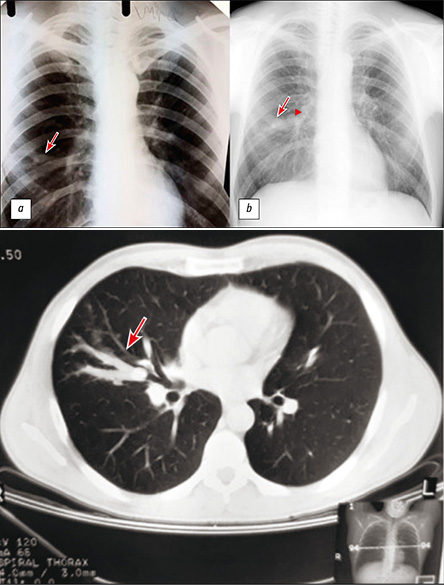

Long-term broncocele anamnesis, triggered by typical carcinoid

The paper presents a case of a single bronchocele (bronchogenic retention cyst) caused by a typical carcinoid that was observed for a long time. During the initial complex examination, including computed tomography with intravenous contrast, fibrobronchoscopy, and immunological and bacteriological examinations of tuberculosis, there were no changes for the oncological and infectious nature. The changes were interpreted as the result of a postponed nonspecific inflammatory process. Most of them were monitored using chest X-ray and the changes were stable. After 15 years, a control chest X-ray revealed an increase in the size of the compaction in the lung and the appearance of a mass with calcification in the medial sections of the compaction zone. Additional examination, including computed tomography with biopsy, determined that the obstruction of the bronchus was caused by a neoplasm [according to histological examination (typical carcinoid)].

It should be noted that the initial detection of negative study results requires oncological alertness and periodic examinations in dynamics.